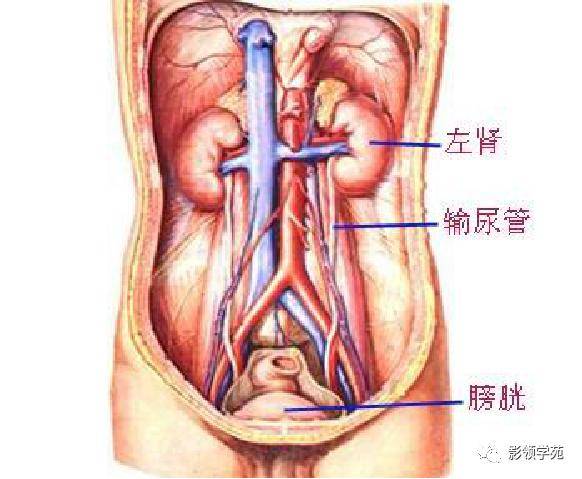

腹部动静脉

腹部动静脉